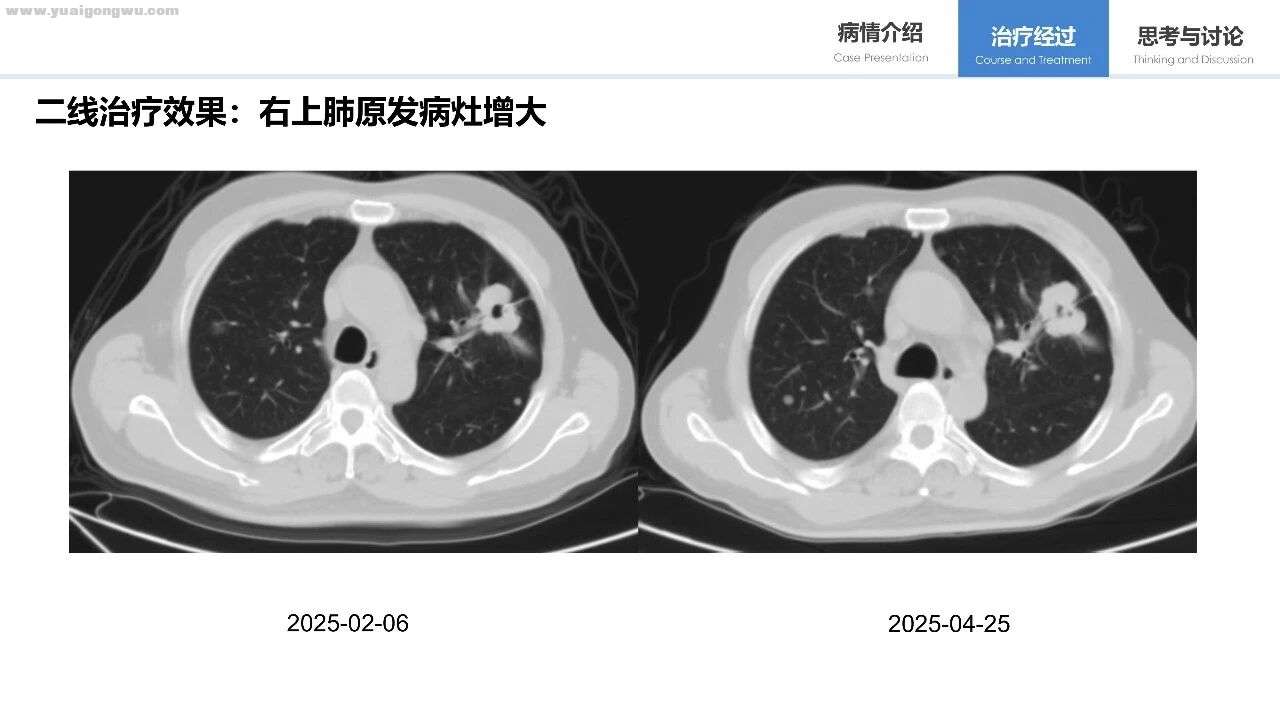

该患者一线PFS约10个月,疗效不甚理想,可能与肿瘤负荷大及合并共突变相关。一线治疗后出现缓慢进展,尝试靶向药加量使PFS进一步延长,后续联合化疗期间,双肺转移病灶经两次影像对比显示有相对快速进展,随即换用依沃西单抗(PD-1/VEGF双特异性抗体)联合培美曲赛、卡铂的化疗方案,这属于EGFR-TKI进展后的标准治疗方案。在此需探讨阿美替尼是否需持续应用,因既往临床研究显示EGFR-TKI与免疫PD-1单抗联合时不良反应可能增加,该问题有待进一步探讨。